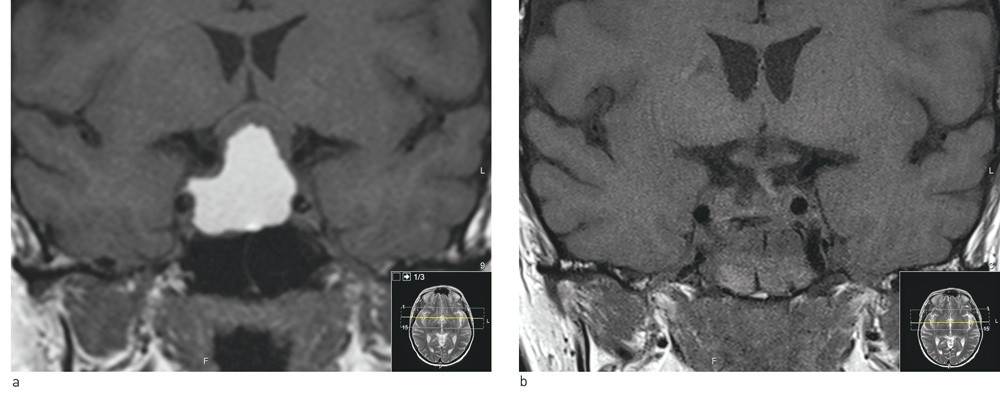

An MRI scan of the pituitary gland (Fig. 1a) revealed a large (31 mm × 29 mm × 26 mm) cystic intracellular tumour, with a large supracellular component that raised the optic nerve decussation. The finding was assumed to represent either a craniopharyngioma or a cystic pituitary macroadenoma.

An MRI scan of the pituitary gland immediately postoperatively (Fig. 1B) showed no sign of residual tumour, and the optic paths were free. The histology results revealed that the tumour was a non-hormone-producing pituitary adenoma with a low level of the proliferation marker ki67.

Figure 1 Coronary T1-weighted MRI images without contrast. a) Large opacity in sella turcica that extends up in the suprasella direction. The optic nerves and optic nerve decussations have been pushed upwards and are seen as a thin, half-moon shaped strip above the tumour. The tumour has a solid component with a low signal just under the optic paths. The large cystic component is seen with a high signal and parallels the internal carotid artery bilaterally. b) Post-operative status. Tumour was removed transphenoidally. There are copious blood products in the sphenoidal sinus. The optic nerves and optic nerve decussations are now lying free and their thickness has normalised. Under them the pituitary stalk is seen in the mid-line with a slight deviation to the left (right in the picture)